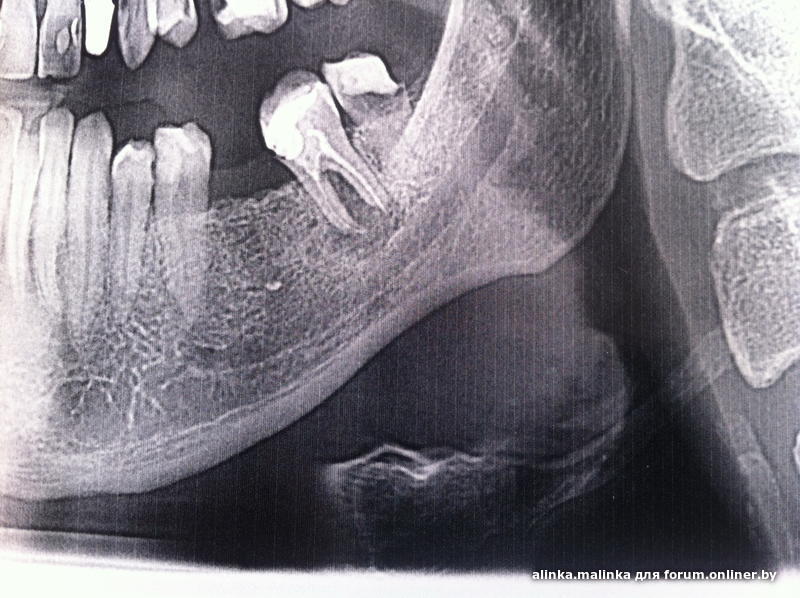

Здравствуйте. Отец собирался ставить имплант на отсутствующую нижнюю шестерку, но около нижней семерки набухла десна и открылся свищ, стоит ли попытаться вылечить эту семерку или тут однозначно удаление?

alinka.malinka, 7 и 8 лучше удалить

Thecbuh, понимаем, что зубу в перспективе хана, но думали что хоть какое-то время еще протянет, удалить никогда не поздно. Там сам зуб никакой или гранулема уже опасная и не подлежит лечению?

а на снимке сами не видите, как зуб классно выпилили в зоне расхождения корней?